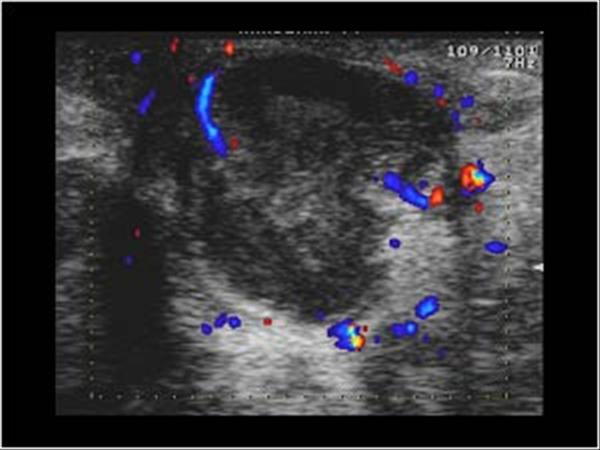

Apxe vú

Apxe vú - Ảnh 3

» Thông tin: Nữ giới – 21 tuổi.

» Lâm sàng: Sưng đau tuyến vú.